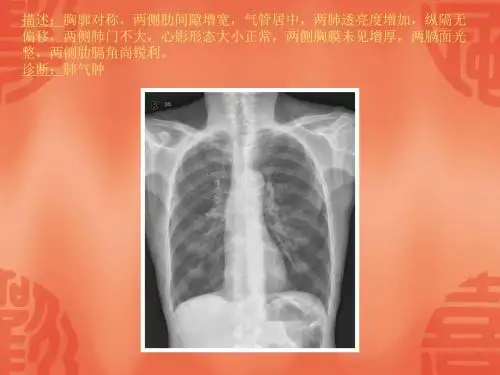

胸部X片主要用于观察肺部、胸膜、纵隔等 结构,是诊断肺部和胸膜疾病的重要手段 。